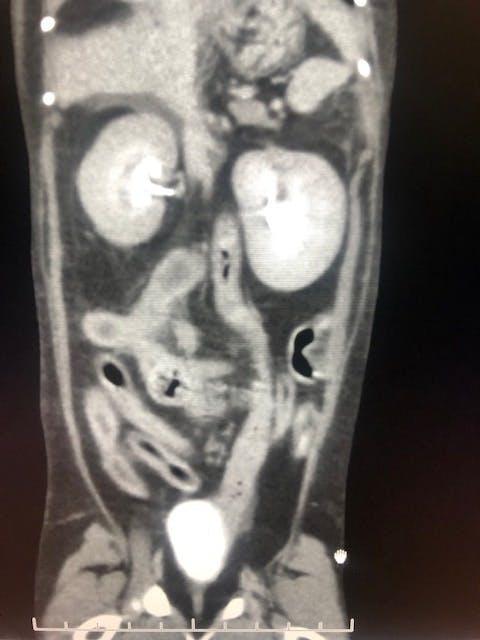

その日のうちに超音波検査、翌日CT検査を実施し膀胱に近い腸に腫瘍があるという事でした。

院長先生曰く、腎臓周りも見え方がおかしいのと腸管の腫瘍からリンパ腫が疑わしいという事で、腸管の腫瘍の切除と腎臓の検査が必要と言われました。

CT検査で院長先生がここが悪いと見せてくれた画像(素人目にはあまりわからなかったです。。)